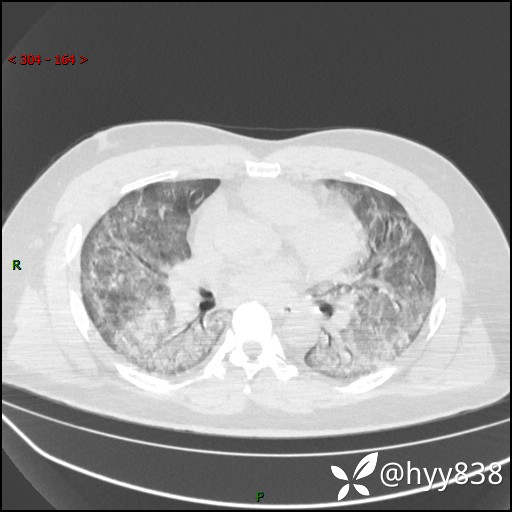

第一次胸部CT